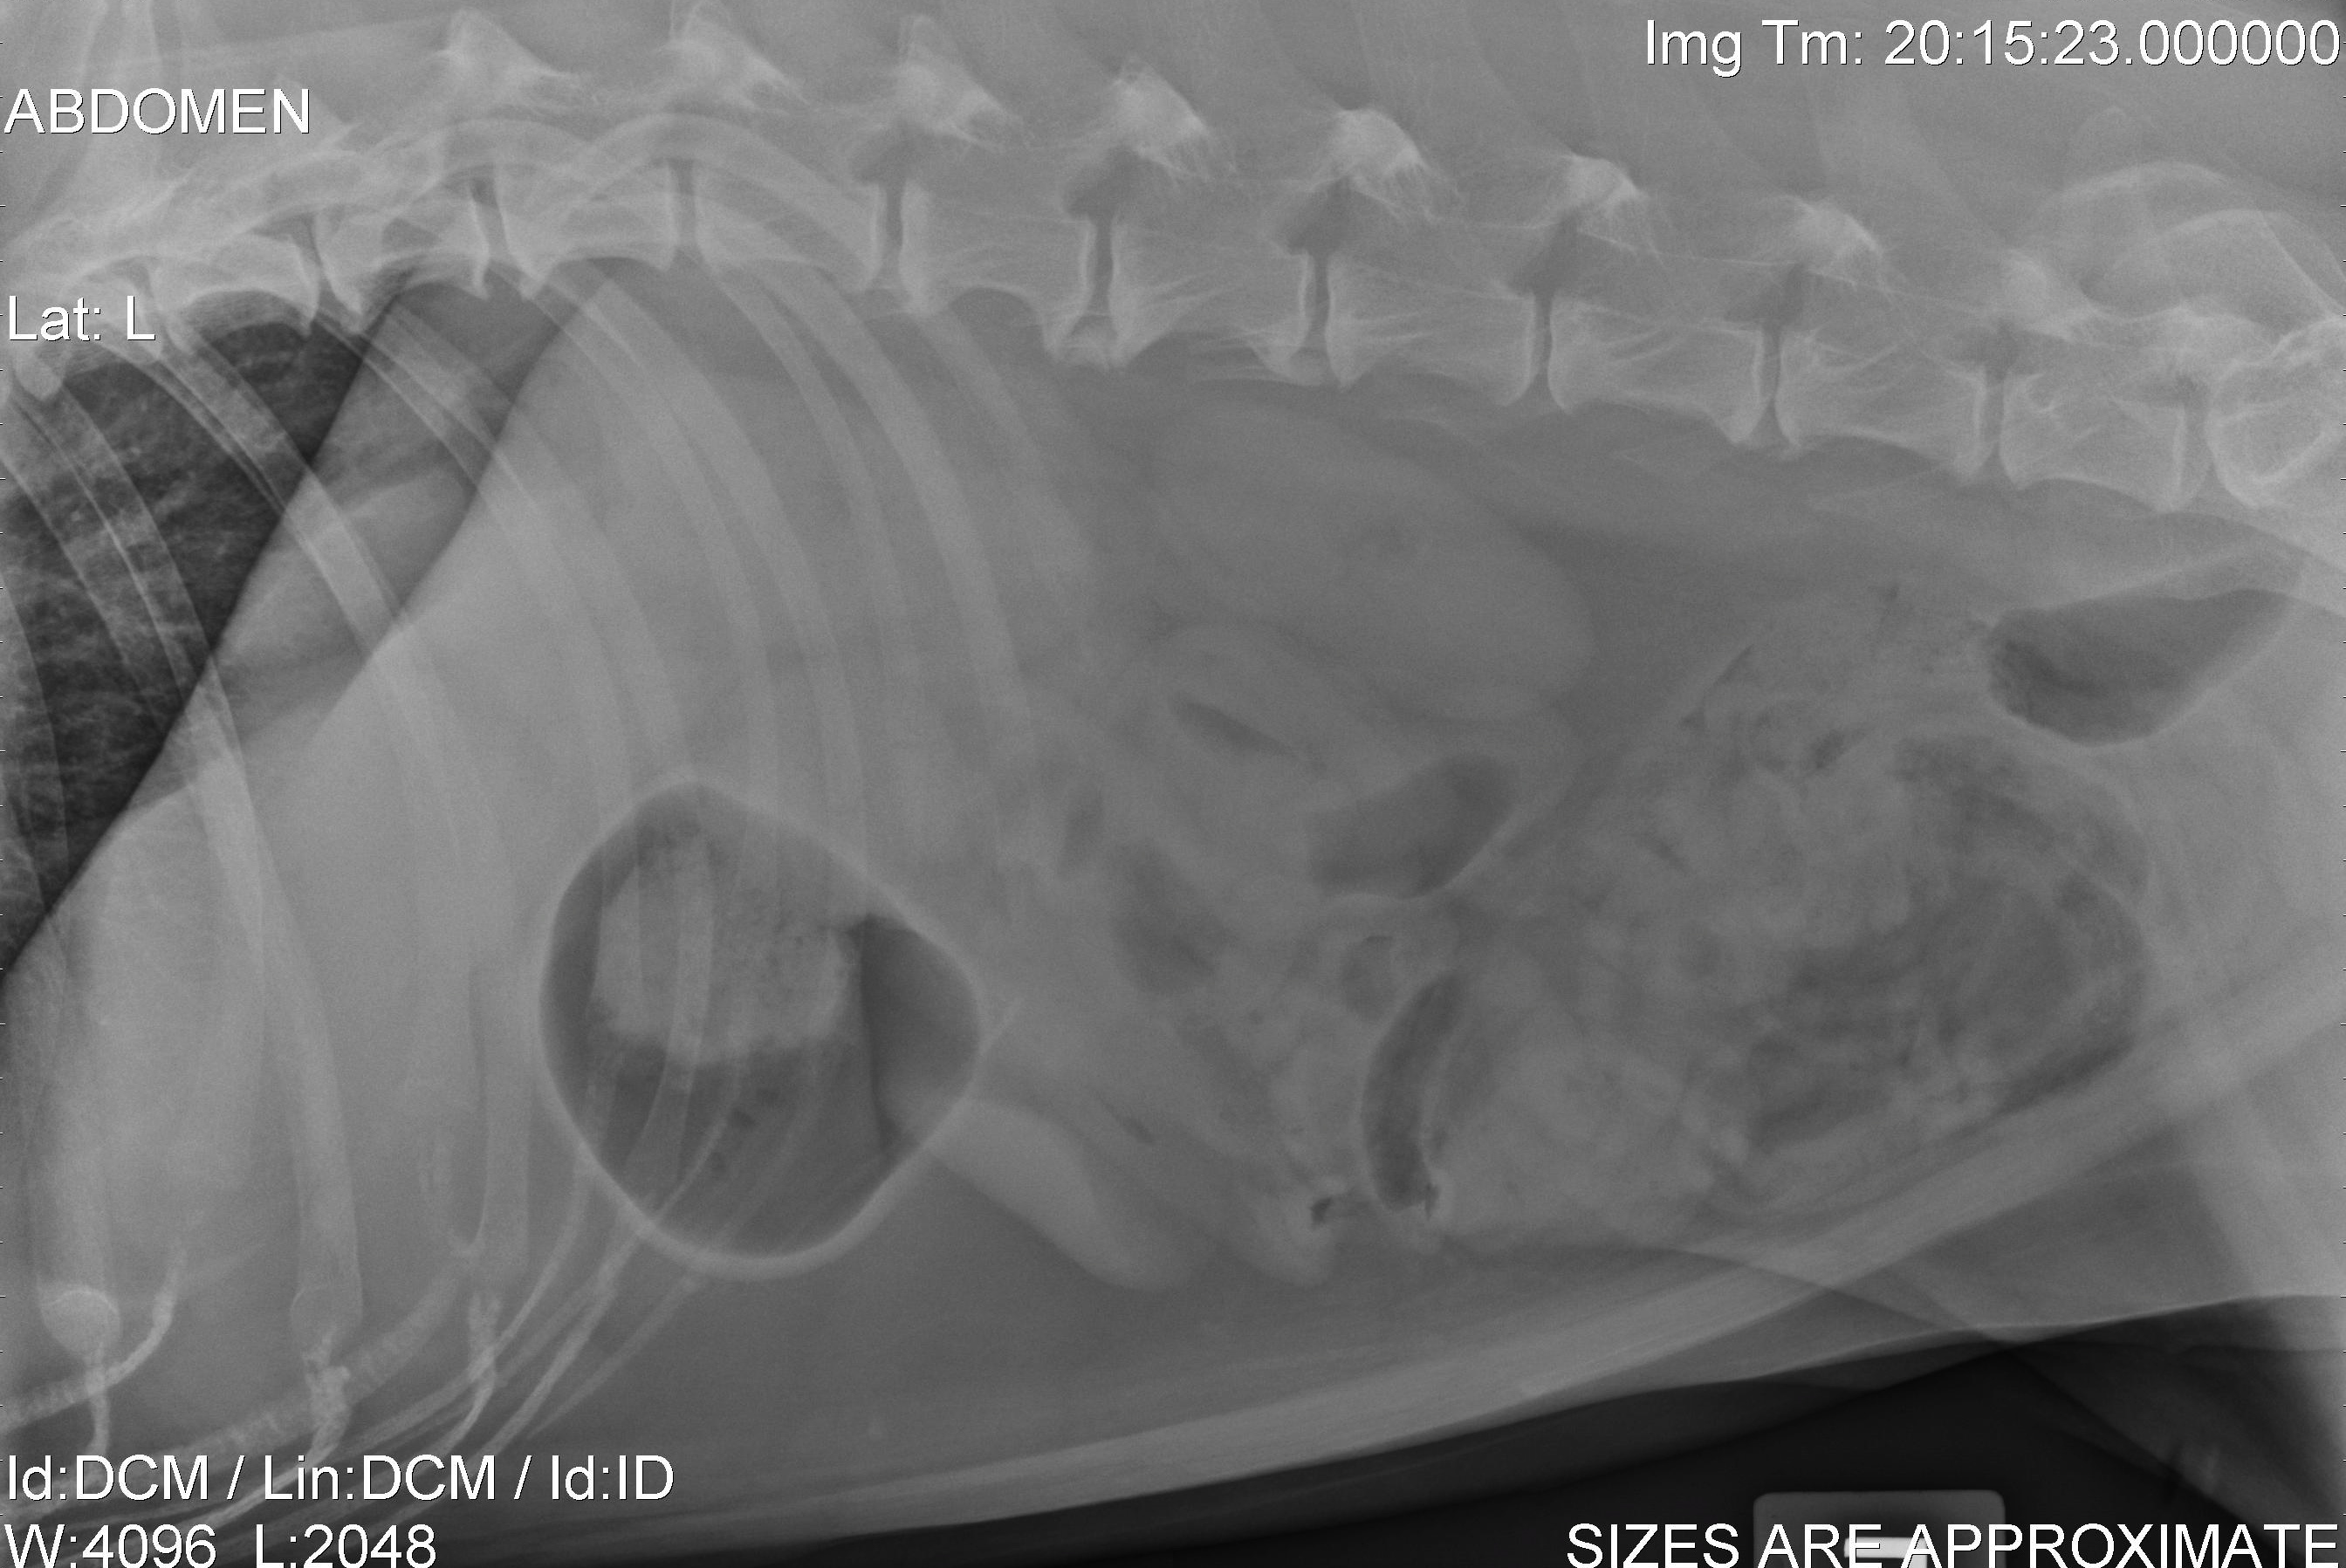

The typical way to diagnose a primary lung tumor is with radiographs (x-rays) of the chest. If a large solitary mass is seen, it is suspected to be a primary lung tumor. Another was to visualize a primary lung tumor would be to perform a CT (computed tomography) scan of the chest. A CT scan gives us excellent detail of the mass and allows a very in depth view of the rest of the lung tissue for evaluation. Some advocate for a fine needle aspirate of the mass (sticking an needle in the mass to get a representative sample of cells) prior to discussing surgery. Typically a solitary lung mass will be a pulmonary adenocarcinoma and a fine needle aspirate will only yield a diagnostic result only 60-70% of the time. Many believe (myself included) that surgery is the next step for a diagnosis. Prior to surgery a minimum staging database should be acquired. This includes (in addition to chest x-rays and/or chest CT scan) complete bloodworm with urinalysis and an abdominal ultrasound (or contrast CT scan). This is to evaluate body organ function and the presence of metastasis or other non-related issues, since most patients with a primary lung tumor fall into the geriatric age category, it is not uncommon to uncover other issues.